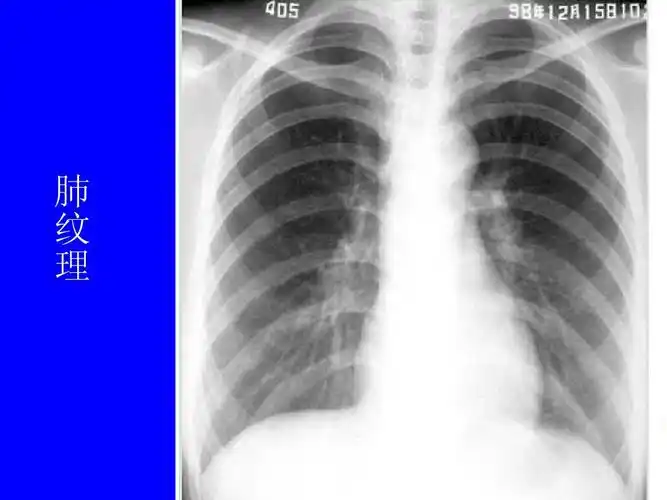

肺部疾病影像学阅片 一,正常胸片 正常胸片(正位片)

影像-正常胸片